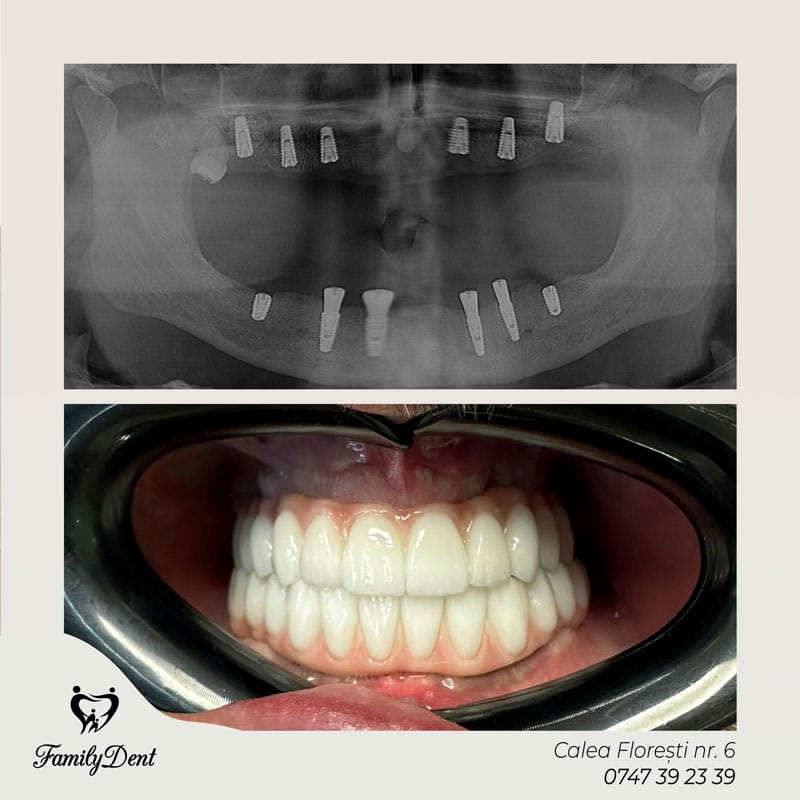

Reabilitarea Totală a Arcadei (All-on-4 și All-on-6)

Dacă îți lipsesc toți dinții, sistemele de tip All-on-4 permit fixarea unei danturi întregi pe doar 4 implanturi strategice. Aceasta elimină necesitatea protezelor mobile, oferind stabilitatea și forța de masticație a dinților naturali.

2. Reabilitări Totale: All-on-4 și All-on-6

Dacă îți lipsesc toți dinții pe o arcadă, sistemele de tip All-on-4 permit fixarea unei danturi complete pe doar 4 sau 6 implanturi. Aceasta este „revoluția” care înlocuiește definitiv proteza mobilă cu una fixă, estetică și funcțională.

Ambele sunt soluții pentru edentația totală. All-on-4 fixează arcada pe 4 implanturi, fiind o soluție minim invazivă, în timp ce All-on-6 folosește 6 implanturi pentru o stabilitate sporită, ideală în cazurile cu resorbție osoasă diferită.